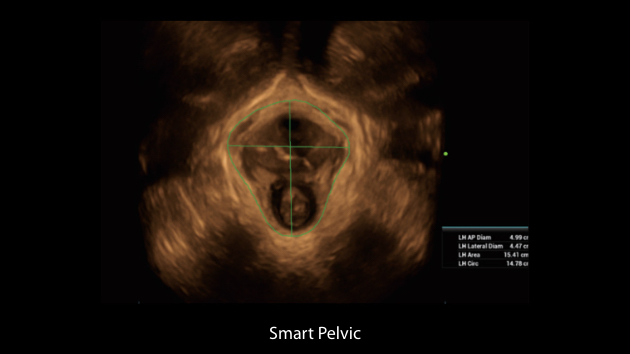

The Nuewa I9, dedicatedly designed for women and neonatal healthcare, providing an innovative experience from inside out.?These innovations are developed based on in-depth insights into complex clinical scenarios, providing accurate and timely answers as well as outstanding efficiency and remarkable user experience.

Clinical Images